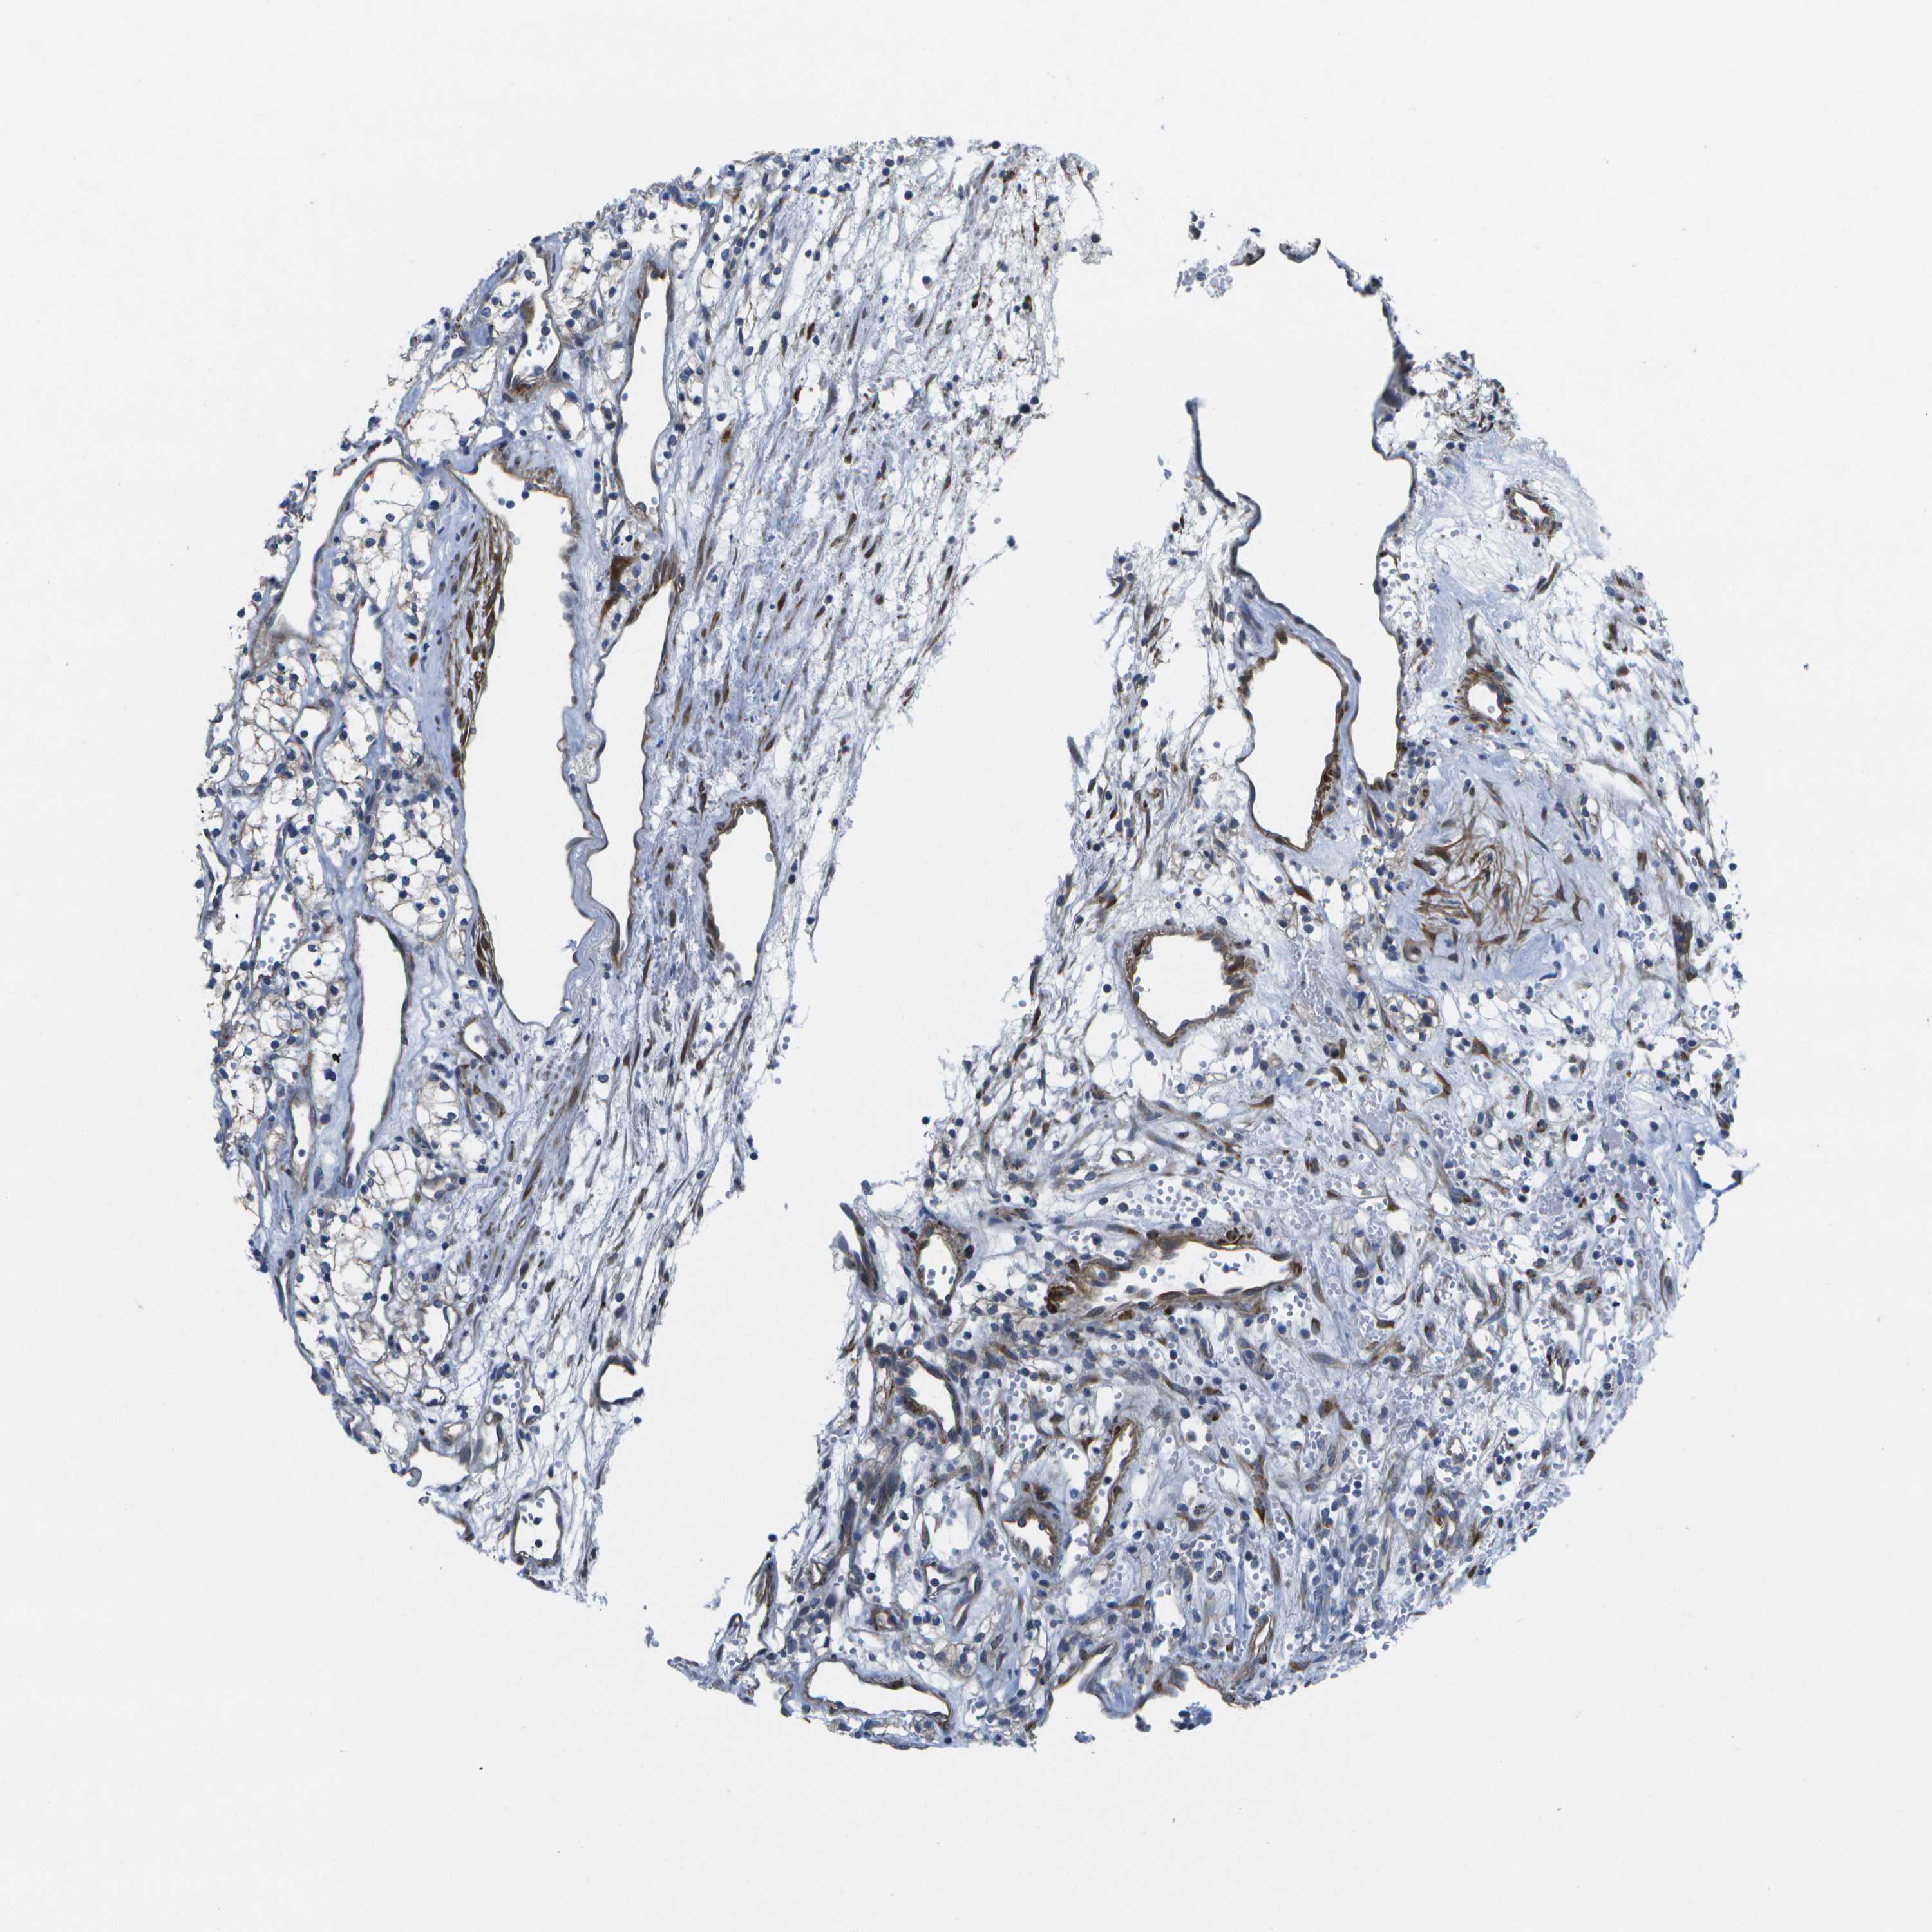

KIDNEY RENAL CLEAR CELL CARCINOMA (VALIDATION) - Interactive survival scatter ploti

The Survival Scatter plot shows the clinical status (i.e. dead or alive) for all individuals in the patient cohort, based on the same data that underlies the corresponding Kaplan-Meier plots. Patients that are alive at last time for follow-up are shown in blue and patients who have died during the study are shown in red.

The x-axis shows the expression levels (FPKM) of the investigated gene in the tumor tissue at the time of diagnosis. The y-axis shows the follow-up time after diagnosis (years). Both axes are complimented with kernel density curves demonstrating the data density over the axes. The top density plot shows the expression levels (FPKM) distribution among dead (red) and alive patients (blue). The right density plot shows the data density of the survived years of dead patients with high and low expression levels respectively, stratified using the cutoff indicated by the vertical dashed line through the Survival Scatter plot. This cutoff is automatically defined based on the FPKM cutoff that minimizes the p-score. The cutoff can be changed by dragging the vertical line or by entering a cutoff value in the square labeled "Current cut-off".

Under the Survival Scatter plot the p-score landscape (black curve; left axis) is shown together with dead median separation (red curve; right axis). Dead median separation is the difference in median mRNA expression between patients who have died with high and low expression, respectively. It is calculated as follows: median FPKM expression of dead patients with high expression - median FPKM expression of dead patients with low expression. This is intended to aid the user in visually exploring custom cutoffs and the associated p-scores and dead median separation.

Individual patient data is displayed and can be filtered by clicking on one or more of the category buttons on the top of the page. Categories describing expression level and patient information include: high, low, alive, dead, female, male and tumor stages. The scale of the x-axis can be toggled between linear and log-scale by clicking on the "x log" button. Mouse-over function shows TCGA ID, patient information and mRNA expression (FPKM) for each patient.

& Survival analysisi

Kaplan-Meier plots summarize results from analysis of correlation between mRNA expression level and patient survival. Patients were divided based on level of expression into one of the two groups "low" (under cut off) or "high" (over cut off). X-axis shows time for survival (years) and y-axis shows the probability of survival, where 1.0 corresponds to 100 percent.

P3H1 is not prognostic in Kidney Renal Clear Cell Carcinoma (validation)

Best expression cut offi

: 22.5

P scorei

N/A

TCGA RNA samplesi

Average pTPM 20.6

Number of samples 100